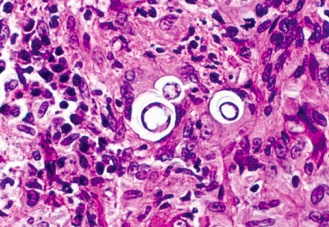

soap bubbles on head: Causes "soap bubble" lesions in gray matter

soap bubbles on lung: Diagnose with a microscopic exam of bronchopulmonary washing

red and silver stripes: Diagnosis of pulmonary Crypto can be aided by mucicarmine or methenamine silver stain